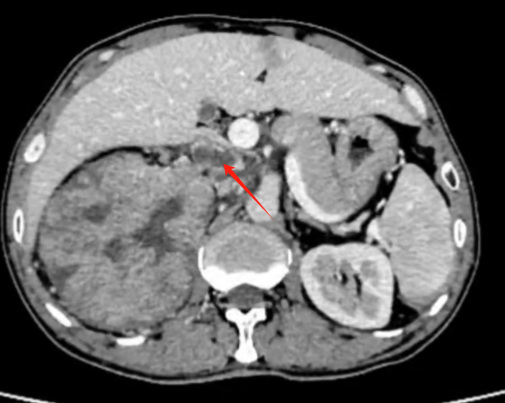

近期,西安交通大学第二附属医院泌尿外科副主任付德来领衔的肾肿瘤团队在一天内成功实施了两例机器人辅助肾癌合并静脉瘤栓手术。手术顺利,术后患者恢复良好,已康复出院。

在泌尿外科领域,肾癌合并静脉瘤栓手术无疑是一块难啃的 “硬骨头”,堪称手术中的 “珠穆朗玛峰”。这一手术的难度超乎想象,术中需要直面人体最粗壮血管的暴露、切开以及精细缝合等诸多棘手环节,每一步操作都如同在悬崖峭壁上行走,稍有不慎,便可能引发严重后果,极高的风险使其当之无愧地被视作泌尿外科手术 “皇冠上的明珠”。

我院泌尿外科团队在肾癌伴癌栓手术治疗方面积累了丰富经验,10余年前既开展了四级癌栓手术(癌栓从肾静脉延伸至右心房)。既往肾癌伴癌栓手术大部分为开放手,创伤大、出血多,患者恢复慢,达芬奇手术机器人让癌栓手术变得更加微创和精准。近年来我院累计完成机器人肾癌伴癌栓手术50余例,完成手术数量和质量均居西北前列。

作为肾肿瘤亚专业组带头人,付德来副主任医师谈到,在肾癌合并静脉瘤栓的手术领域,机器人技术展现出了极为显著的优势。其配备的超高清裸眼 3D 镜头,拥有高达 10 倍的放大效能,能够将组织内部的细微结构清晰地呈现于术者眼前,仿佛开启了微观世界的大门,让每一处关键细节都无所遁形。不仅如此,机器人所独具的机械臂结构更是一大亮点,既稳定可靠,又具备超乎寻常的灵活性,面对复杂的人体解剖结构,它能够游刃有余地实现精细解剖操作,精准抵达那些传统手术器械难以企及的细微区域。